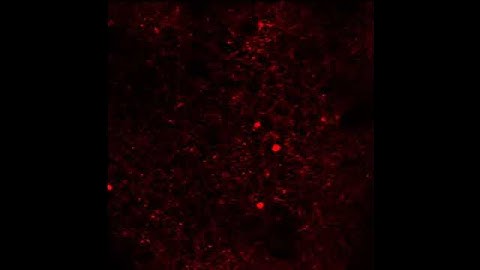

3D Reconstruction of Cortical Neurons from Multi-photon Resonant Scan Imaging in NEX-tdTomato